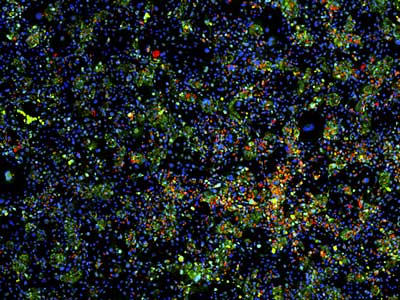

此前,这组研究人员曾开发了一种方法,将肝细胞与小鼠成纤维细胞精确混合,从而在体外维持肝细胞的正常功能。研究人员对此系统进行了改进,并在其中对12,500种化合物进行了大规模筛选,分析这些化合物对肝细胞生长和功能的影响。

肝脏是人体内的重要器官,具有多种功能,包括药物解毒作用、能量代谢、蛋白合成和胆汁生产等。研究人员对83种肝脏酶的表达水平进行了检测,以此评估肝细胞 的功能。他们筛选了八名组织捐献者的数千个肝细胞,鉴定了能维持细胞功能或促进细胞分裂的12种化合物。其中有两种化合物,对年轻捐献者的细胞效果特别 好。